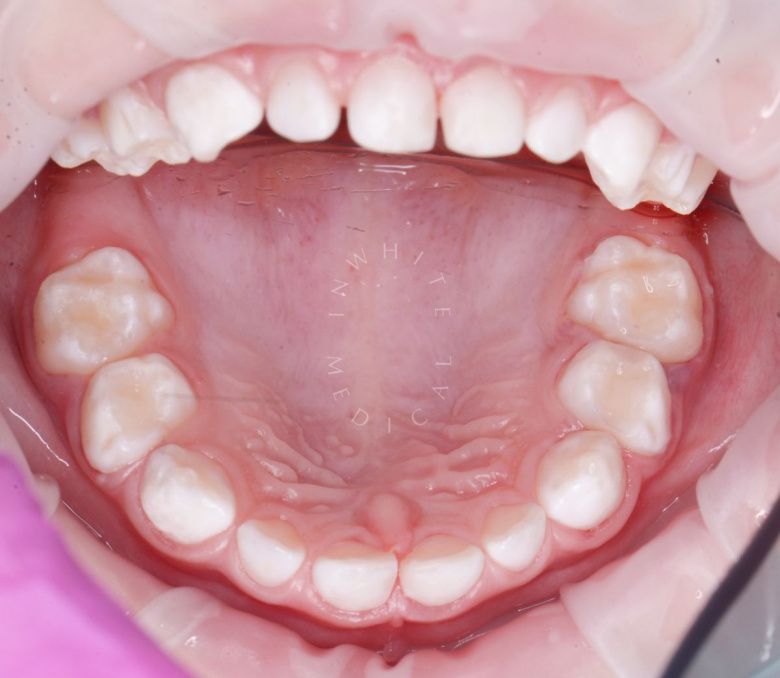

етская стоматология под наркозом Москва. Лечение молочных зубов и установка металлических коронок во сне - до процедуры